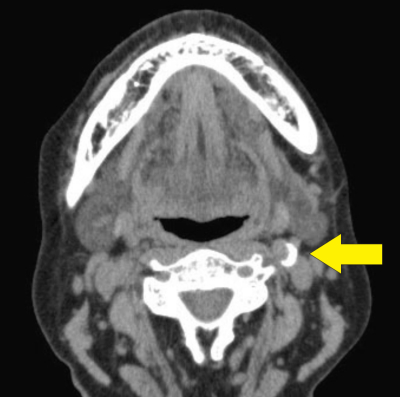

高齢者のCTを別に示す。矢印で示す石灰化が認められるのはどれか。1つ選べ。

c. 内頸動脈

高齢者の動脈硬化→石灰化。